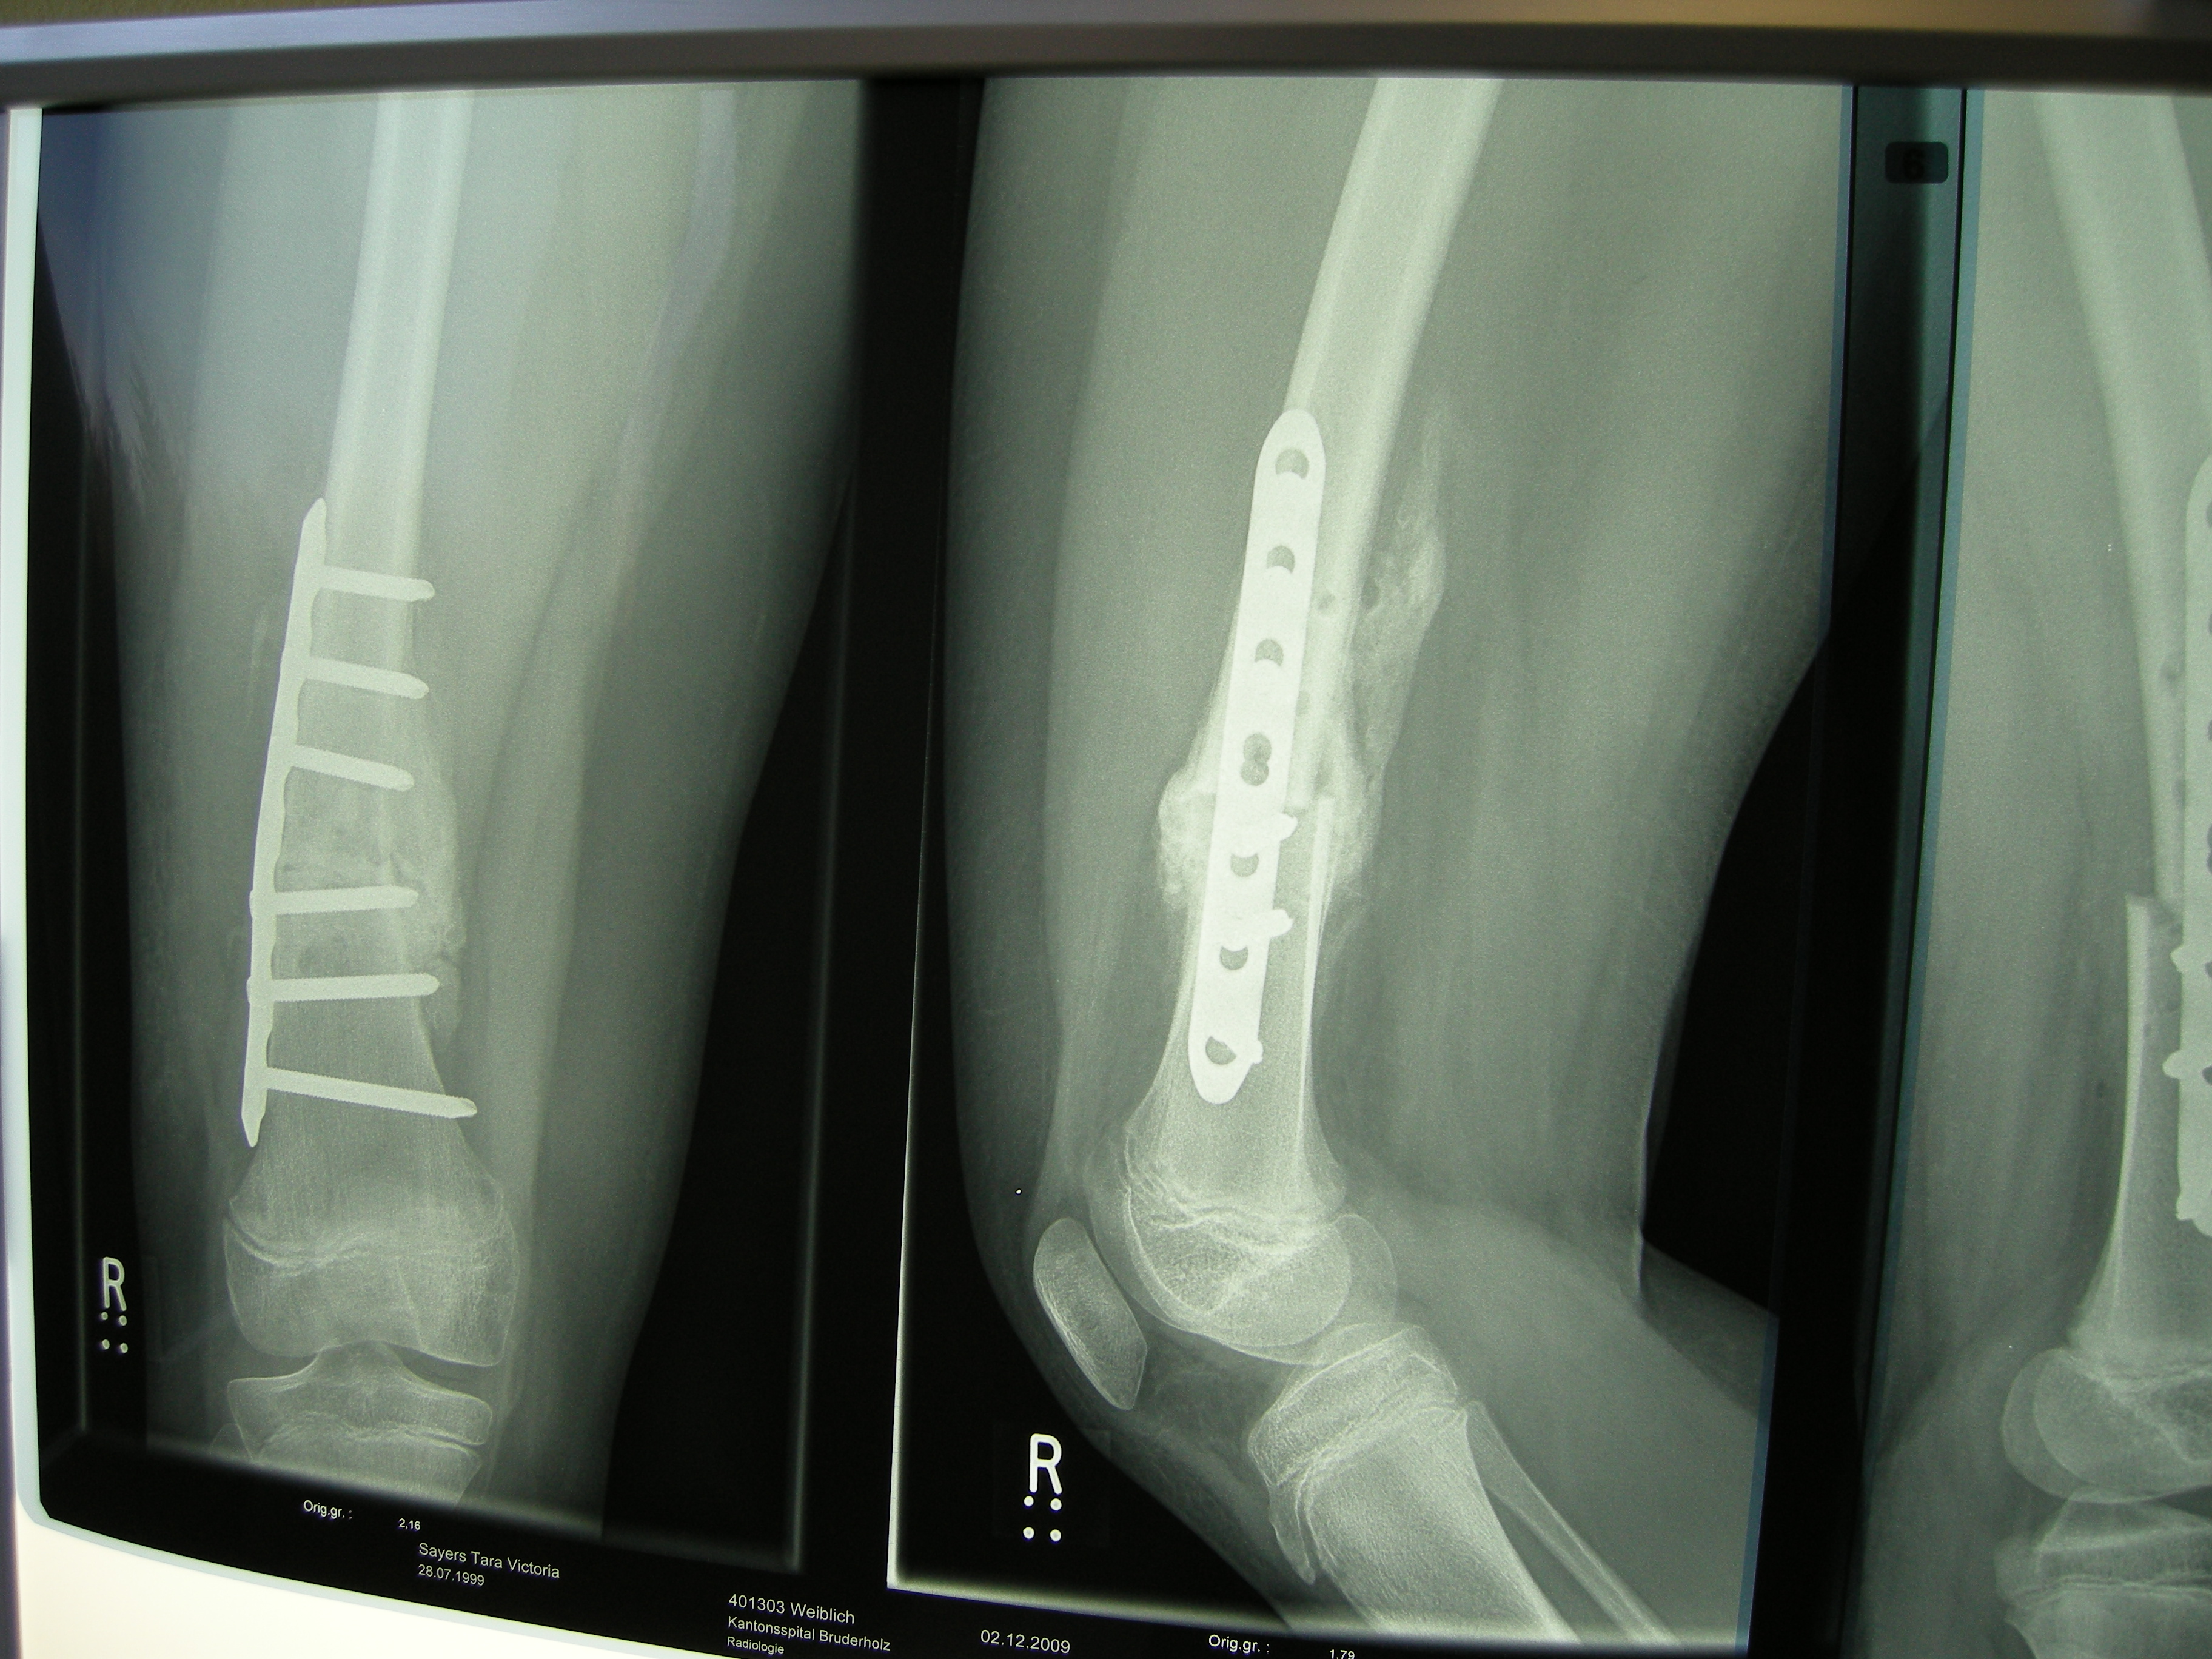

XRays

2009